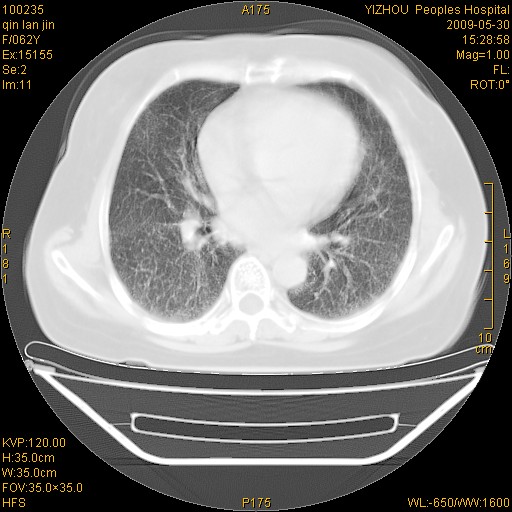

标题: CT20268:肺泡癌?间质性肺炎? [打印本页]

标题: CT20268:肺泡癌?间质性肺炎?

女,62岁,近二年经常咳嗽,近二个月,消瘦、乏力。

两肺弥漫性间质性病变(间质性肺炎伴肺间质纤维化?)。

弥漫性双肺间质纤维化

支持弥漫性肺间质纤维化。

支持 特发性间质性肺炎【iip 】

纵隔淋巴结大,须排外癌性淋巴管炎